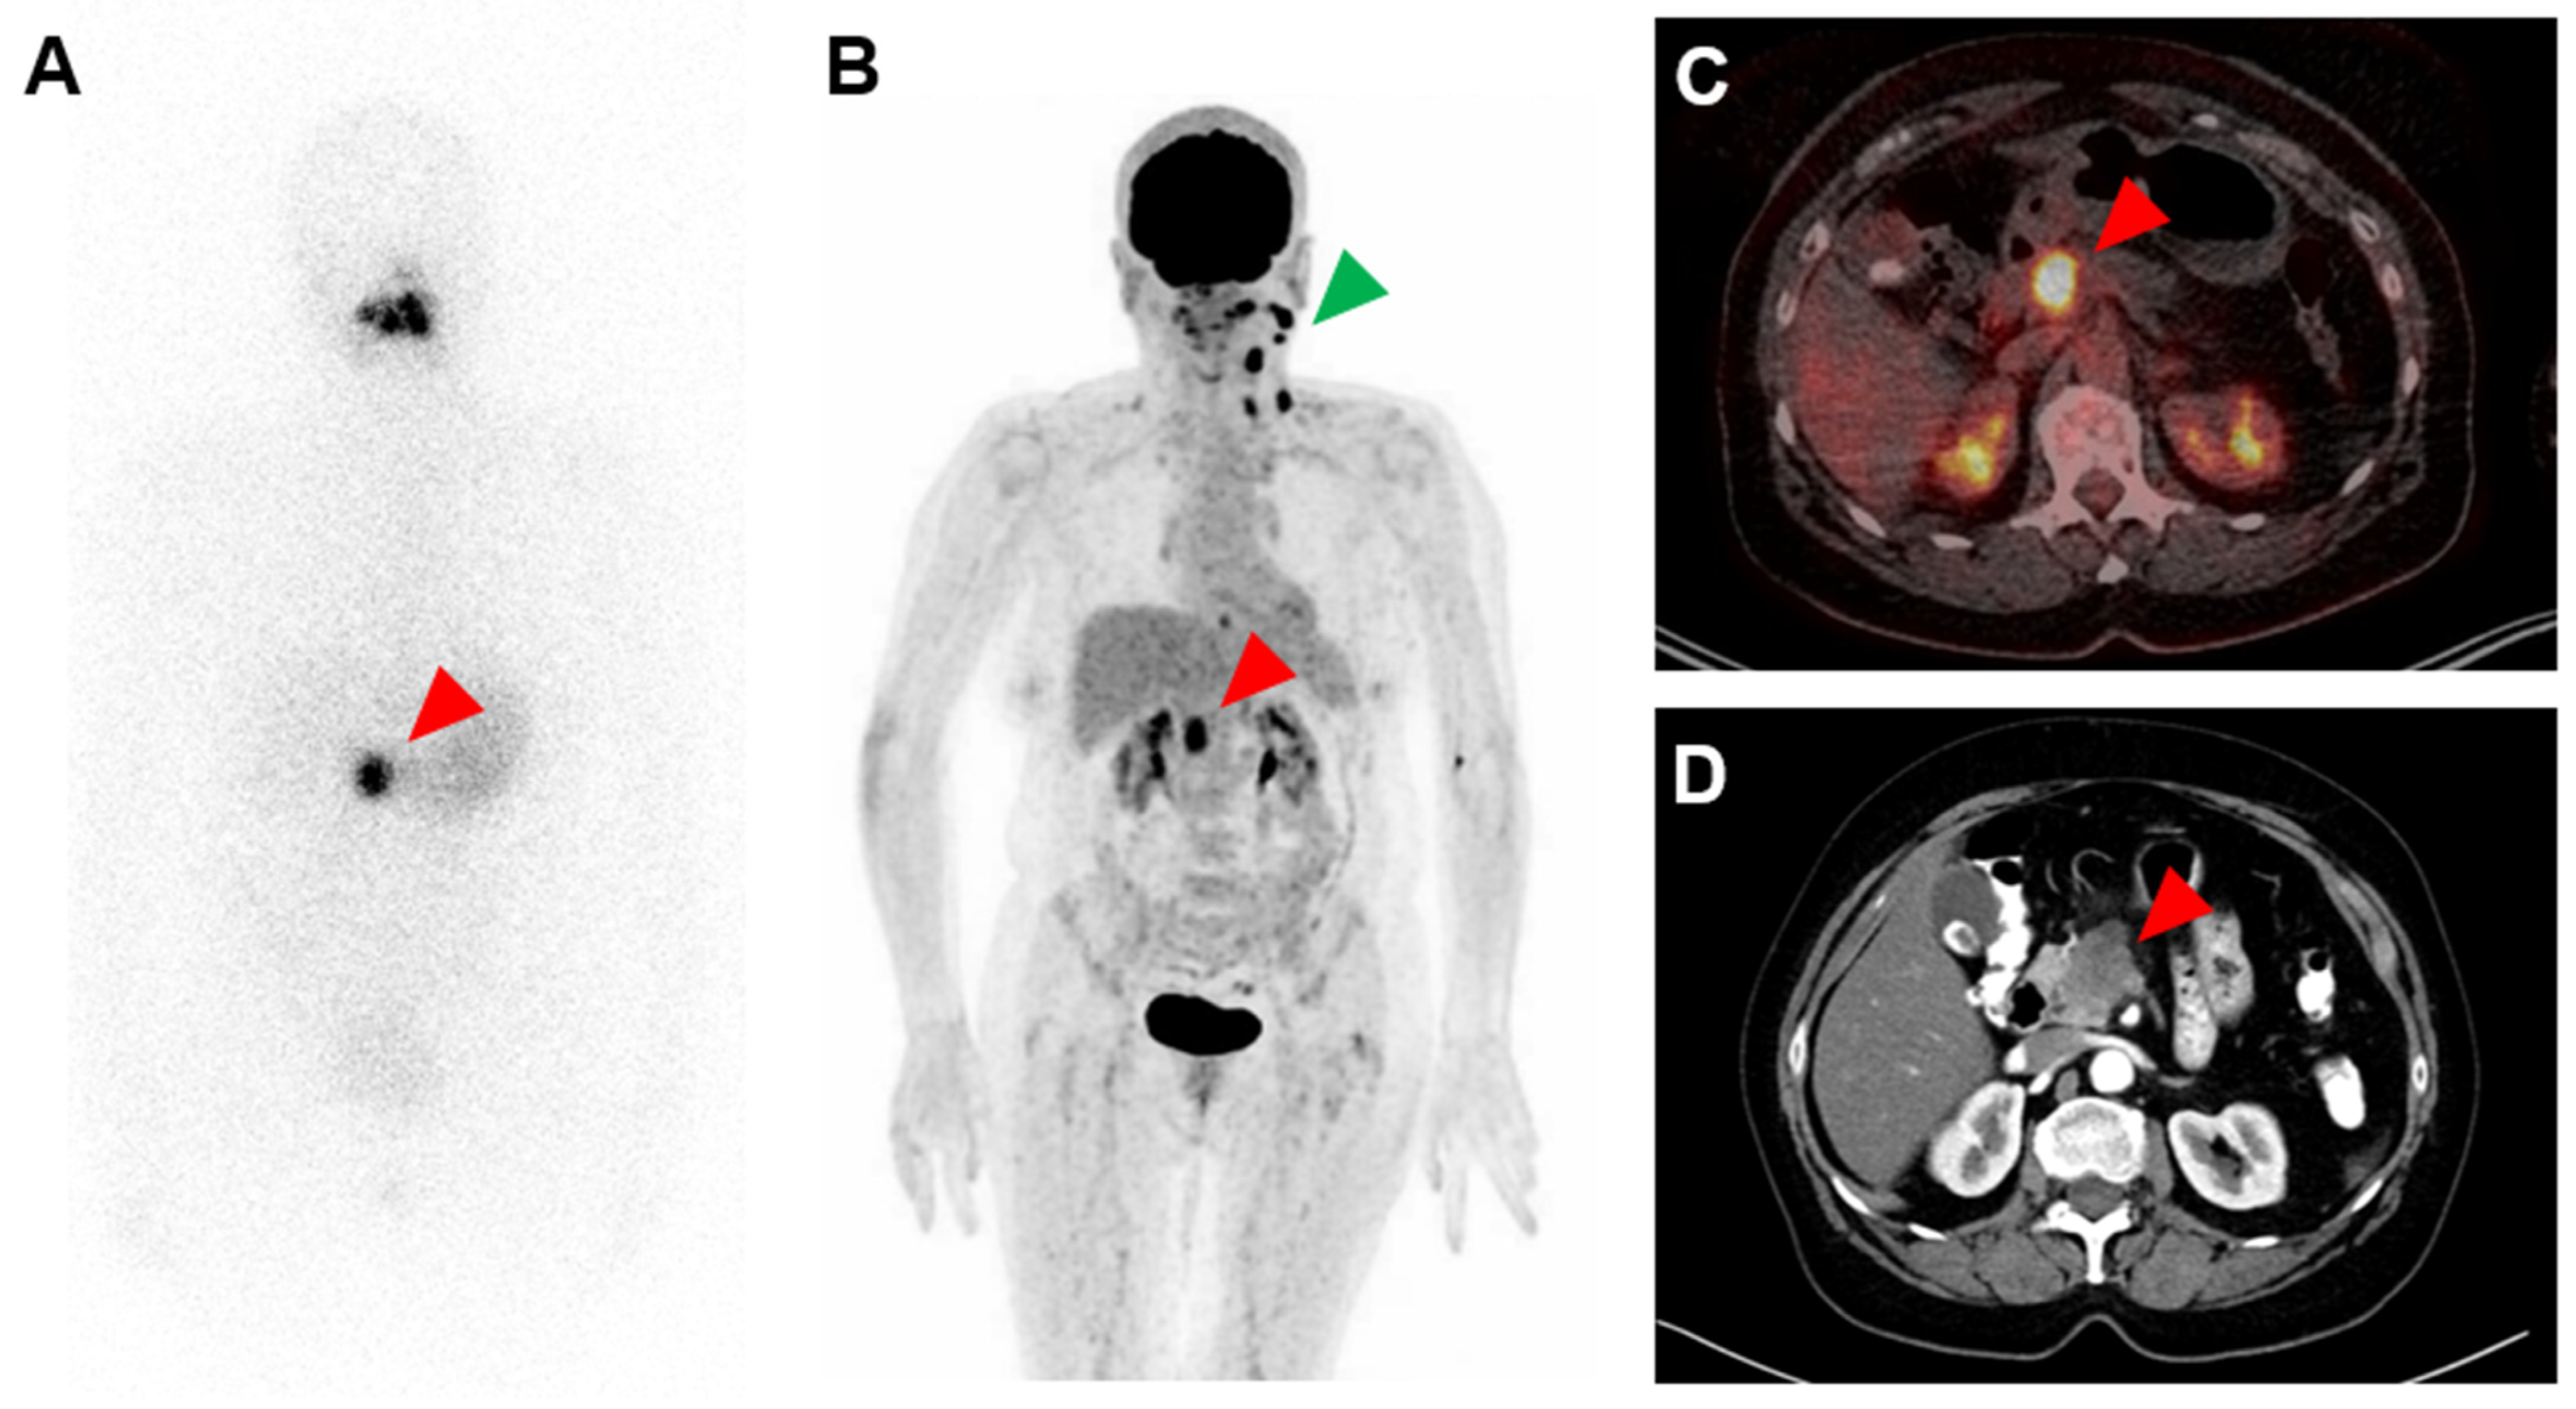

Strongly Radioiodine-Positive Pancreatic Adenocarcinoma Mimicking Metastasis of Differentiated Thyroid Cancer

Rosar, F.; Burgard, C.; Linxweiler, M.; Stahl, P.R.; Khreish, F.; Ezziddin, S. Strongly Radioiodine-Positive Pancreatic Adenocarcinoma Mimicking Metastasis of Differentiated Thyroid Cancer. Diagnostics 2022, 12, 1934. https://doi.org/10.3390/diagnostics12081934